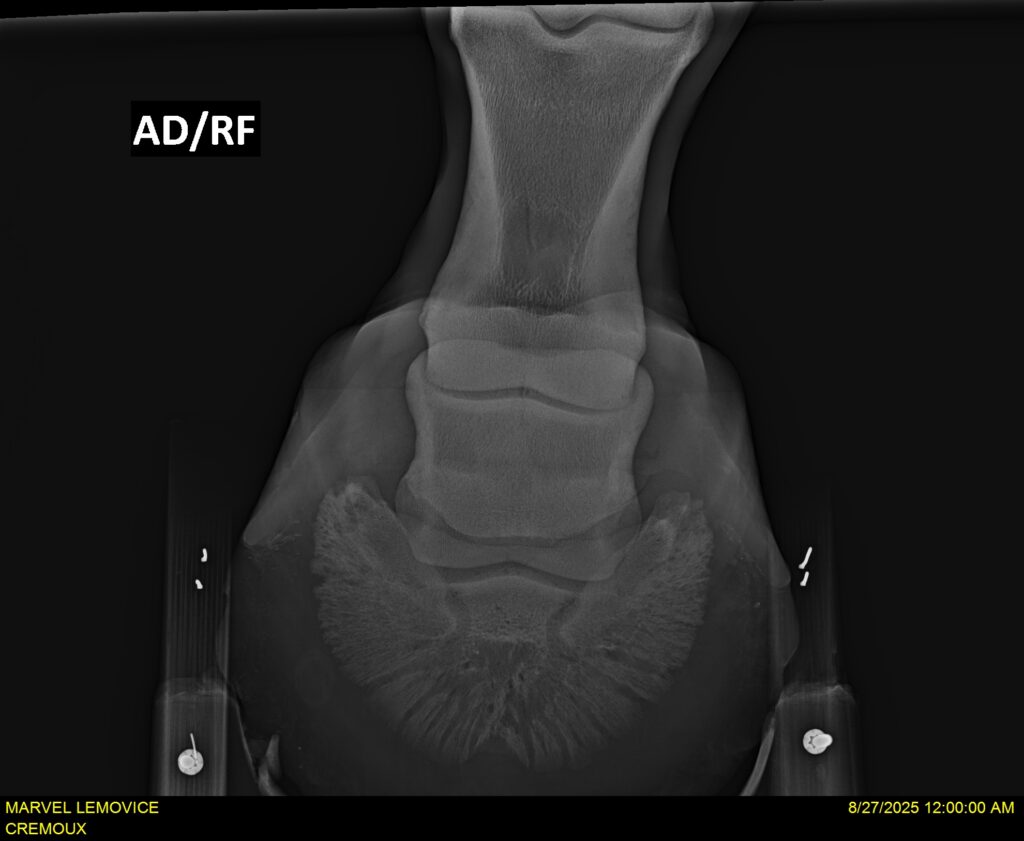

MARVEL LEMOVICE, hongre, Selle Français prend 4 ans en 2026. POPSTAR LOZONAIS x ROSIRE sur une excellente souche maternelle de l’élevage PLATIERE. Débourré aux trois allures et mise en route à l’obstacle. Super modèle avec du cadre et de la force, cheval respectueux avec des moyens. Très agréable au quotidien. Transport OK, maréchalerie OK, santé RAS, Bilan 20 clichés radios + clinique OK.

RADIOS ET CLINIQUE